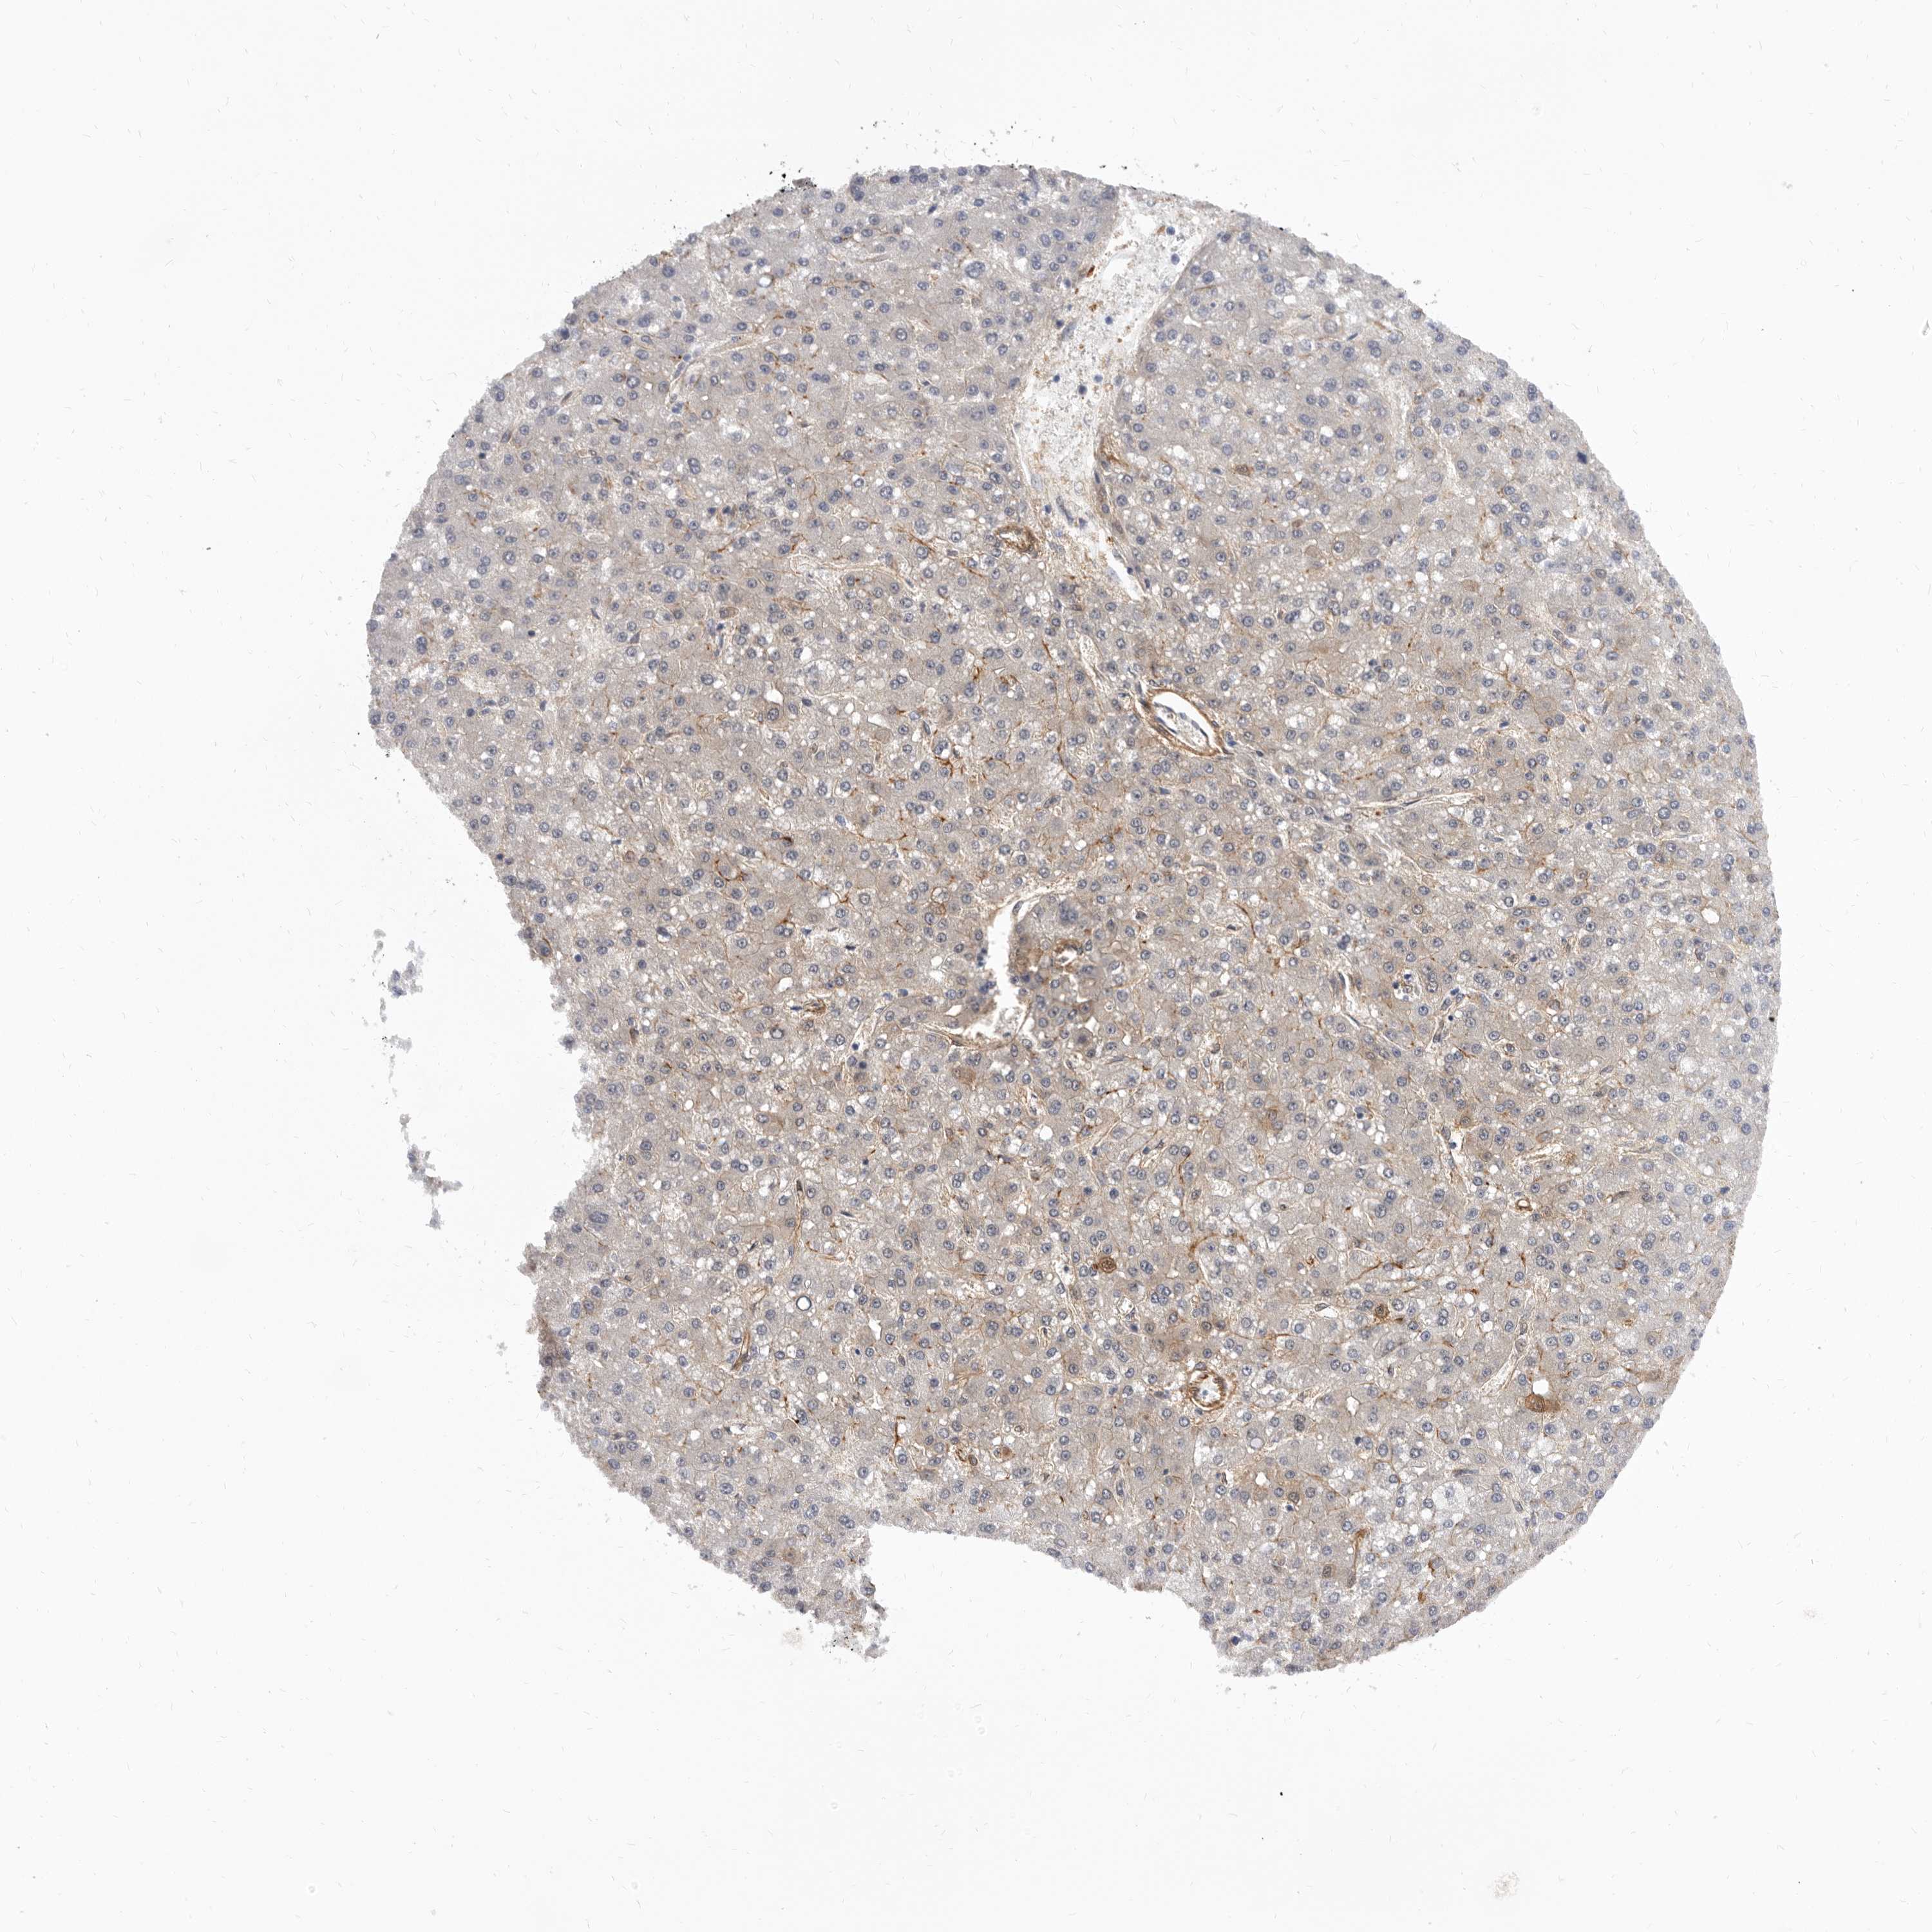

LIVER CANCER - Protein expressioni

A mouse-over function shows sample information and annotation data. Click on an image to view it in a full screen mode. Samples can be filtered based on level of antibody staining by selecting one or several of the following categories: high, medium, low and not detected. The assay and annotation is described here.

Antibody stainingi

Antibody staining in the annotated cell types in the current human tissue is reported as not detected, low, medium, or high, based on conventional immunohistochemistry profiling in selected tissues. This score is based on the combination of the staining intensity and fraction of stained cells.

Each image is clickable and will lead to virtual microscopy that enables deeper exploration of all samples and also displays staining intensity scores, fraction scores and subcellular localization as well as patient and tissue information for each sample.

Antibody HPA028448

Antibody HPA028696

Staining

High

Medium

Low

Not detected

Intensity

Strong

Moderate

Weak

Negative

Quantity

>75%

75%-25%

<25%

None

Location

Nuclear

Cytoplasmic/membranous

Cytoplasmic/membranous,nuclear

Cholangiocarcinoma

Carcinoma, Hepatocellular, NOS